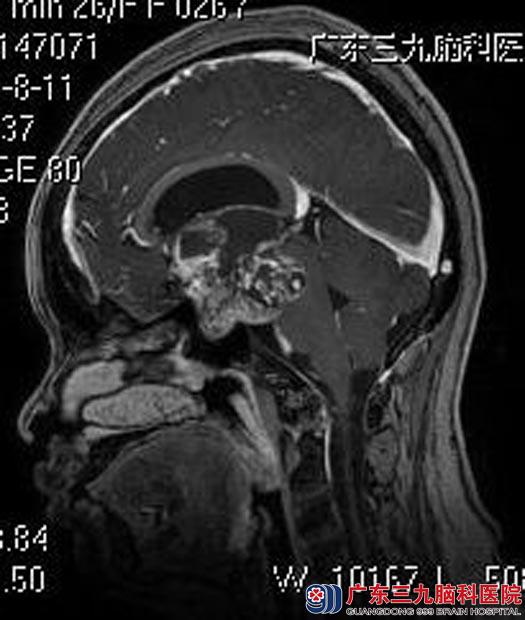

广东三九脑科医院MR检查提示:鞍区示一不规则形囊实性占位性病变,4.7cm×3.9cm×3.7cm;病变向上突入第三脑室,向后推压脑干受压变形。垂体明显受压变薄,视交叉及垂体柄受压显示不清。考虑颅咽管瘤可能性大,伴幕上梗阻性脑积水(轻度)。

由综合神经外科鲁明主任主刀,在全麻下行经额视交叉前终板联合入路鞍区巨大颅咽管瘤切除术,术中见肿瘤呈灰白色,质软,部分钙化,镜下行肿瘤切除,术中对嗅神经、视神经保护完好,手术顺利结束。术后王女士泌乳症状明显好转,无明显尿崩、离子等术后并发症。术后病理结果提示:颅咽管瘤。